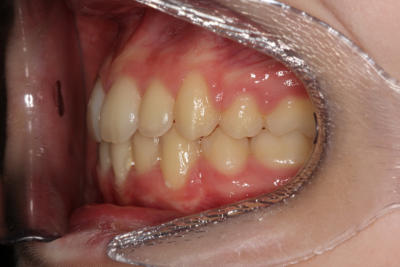

Crowding – Child case